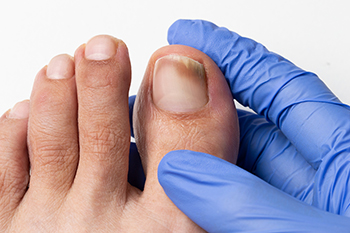

When Thick Yellow Toenails Signal a Fungal Infection

Toenail fungus is a common condition that often begins quietly. You may first notice a small white or yellow spot under the nail. Over time, the nail can become thick, brittle, discolored, and difficult to trim. Some nails may lift from the nail bed or develop a crumbly texture. Warm, moist environments inside shoes create an ideal setting for fungal growth. People who use public pools, share nail tools, or have diabetes are at higher risk. Treatment depends on the severity of the infection. Mild cases may respond to prescription topical medications applied daily. More advanced infections often require oral antifungal medicine to reach the fungus beneath the nail. In certain situations, partial nail removal may be recommended to allow better healing. Early care improves the chance of clearing the infection and preventing spread to other nails. If you notice persistent toenail changes, it is suggested that you see a podiatrist for a proper diagnosis and appropriate treatment.

Fungal infection of the toenail, or onychomycosis, typically appears as a gradual change in a toenail’s texture and color that involves brittleness and darkening. The fungal infection itself occurs beneath the surface of the nail. Aside from discoloration, other symptoms include the collection of debris beneath the nail plate, white marks on the nail plate, and a foul odor emanating from the nail. If ignored, the infection can spread into other nails and the skin; in severe cases, it can hinder one’s ability to work or walk.